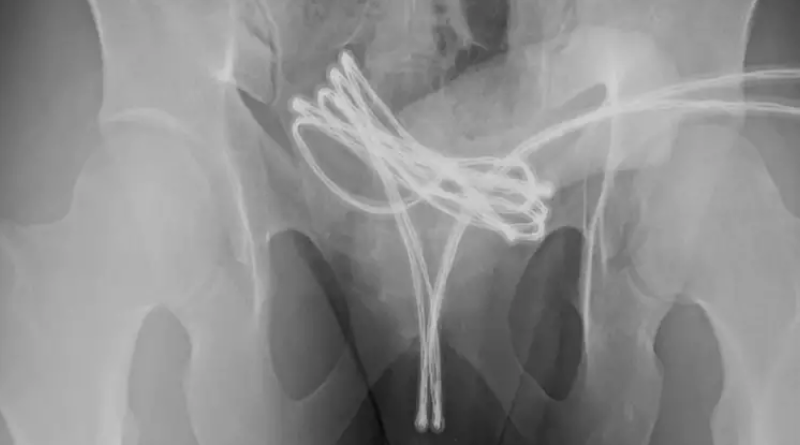

O paciente sofreu apenas ferimentos leves e recebeu alta após tratamento com antibióticos, analgésicos e o uso de um cateter urinário por uma semana (Foto: Cureus)

Após tentativas fracassadas de remoção manual, foi necessário realizar uma cirurgia sob anestesia geral. O procedimento consistiu na introdução de uma câmera pela uretra para localizar e retirar o cabo com o mínimo de danos possíveis.

Após tentativas fracassadas de remoção manual, foi necessário realizar uma cirurgia (Foto: Cureus)